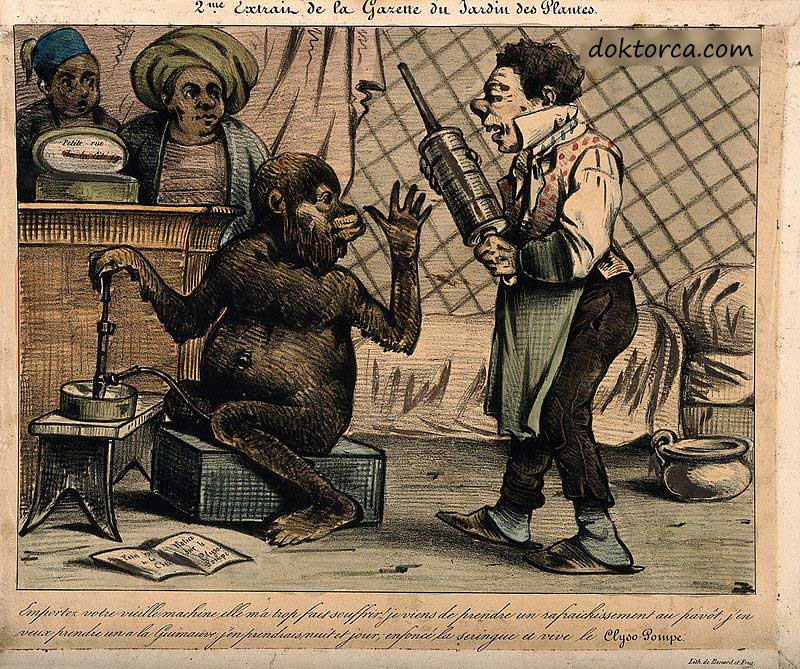

Antik çağlardan beri farklı toplumlar, sağlık hizmeti sağlayıcılarının hastalarda kabızlığa nasıl tepki vermesi gerektiği konusunda tıbbi görüşler yayınladılar. Çeşitli zamanlarda ve yerlerde doktorlar, kabızlığın her türlü tıbbi veya sosyal nedeni olduğunu iddia ettiler. Tarihteki doktorlar, bir spatula mundani kullanımı dahil olmak üzere kabızlığı makul ve mantıksız yollarla tedavi etmişlerdir.

Hastalık mikrop teorisinin ortaya çıkışından sonra, “kendi kendine zehirlenme” fikri, popüler Batı düşüncesine yeni bir yoldan girdi. Bilimsel bir tıbbi tedavi olarak lavman ve alternatif tıbbi tedavi olarak kolon temizliği, tıbbi uygulamada daha yaygın hale geldi.